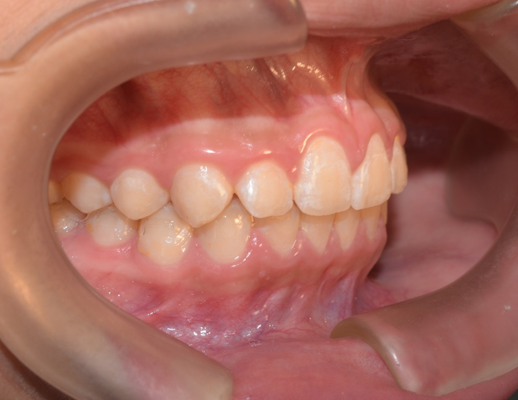

El paciente feliz, al finalizar su tratamiento

Caso de corrección de apiñamiento con ortodoncia fija

Paciente femenino de 13 años de edad, acude a consulta por dientes desalineados en la zona frontal, buscando mejorar la estética de su sonrisa y facilitar la higiene dental.

La paciente en fase inicial de tratamiento

En la evaluación clínica se observaron:

- Apiñamiento anterior superior

- Rotaciones dentales en incisivos laterales

- Desalineación en el sector estético (zona visible al sonreír)

- Relación oclusal susceptible de mejora